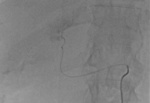

– Metoda, którą stosujemy od ubiegłego roku, polega na tym, że poprzez specjalny cewnik wprowadzony do tętnicy udowej docieramy do wątroby, a następnie do każdej zmiany przerzutowej i bezpośrednio do niej podajemy chemioterapeutyk, jednocześnie zamykając naczynie i odcinając dopływ krwi do guza i tym samym jego odżywianie (ryc. 1, 2) – mówi prof. dr hab. med. Aleksander Falkowski z Zakładu Radiologii Zabiegowej szczecińskiego szpitala.